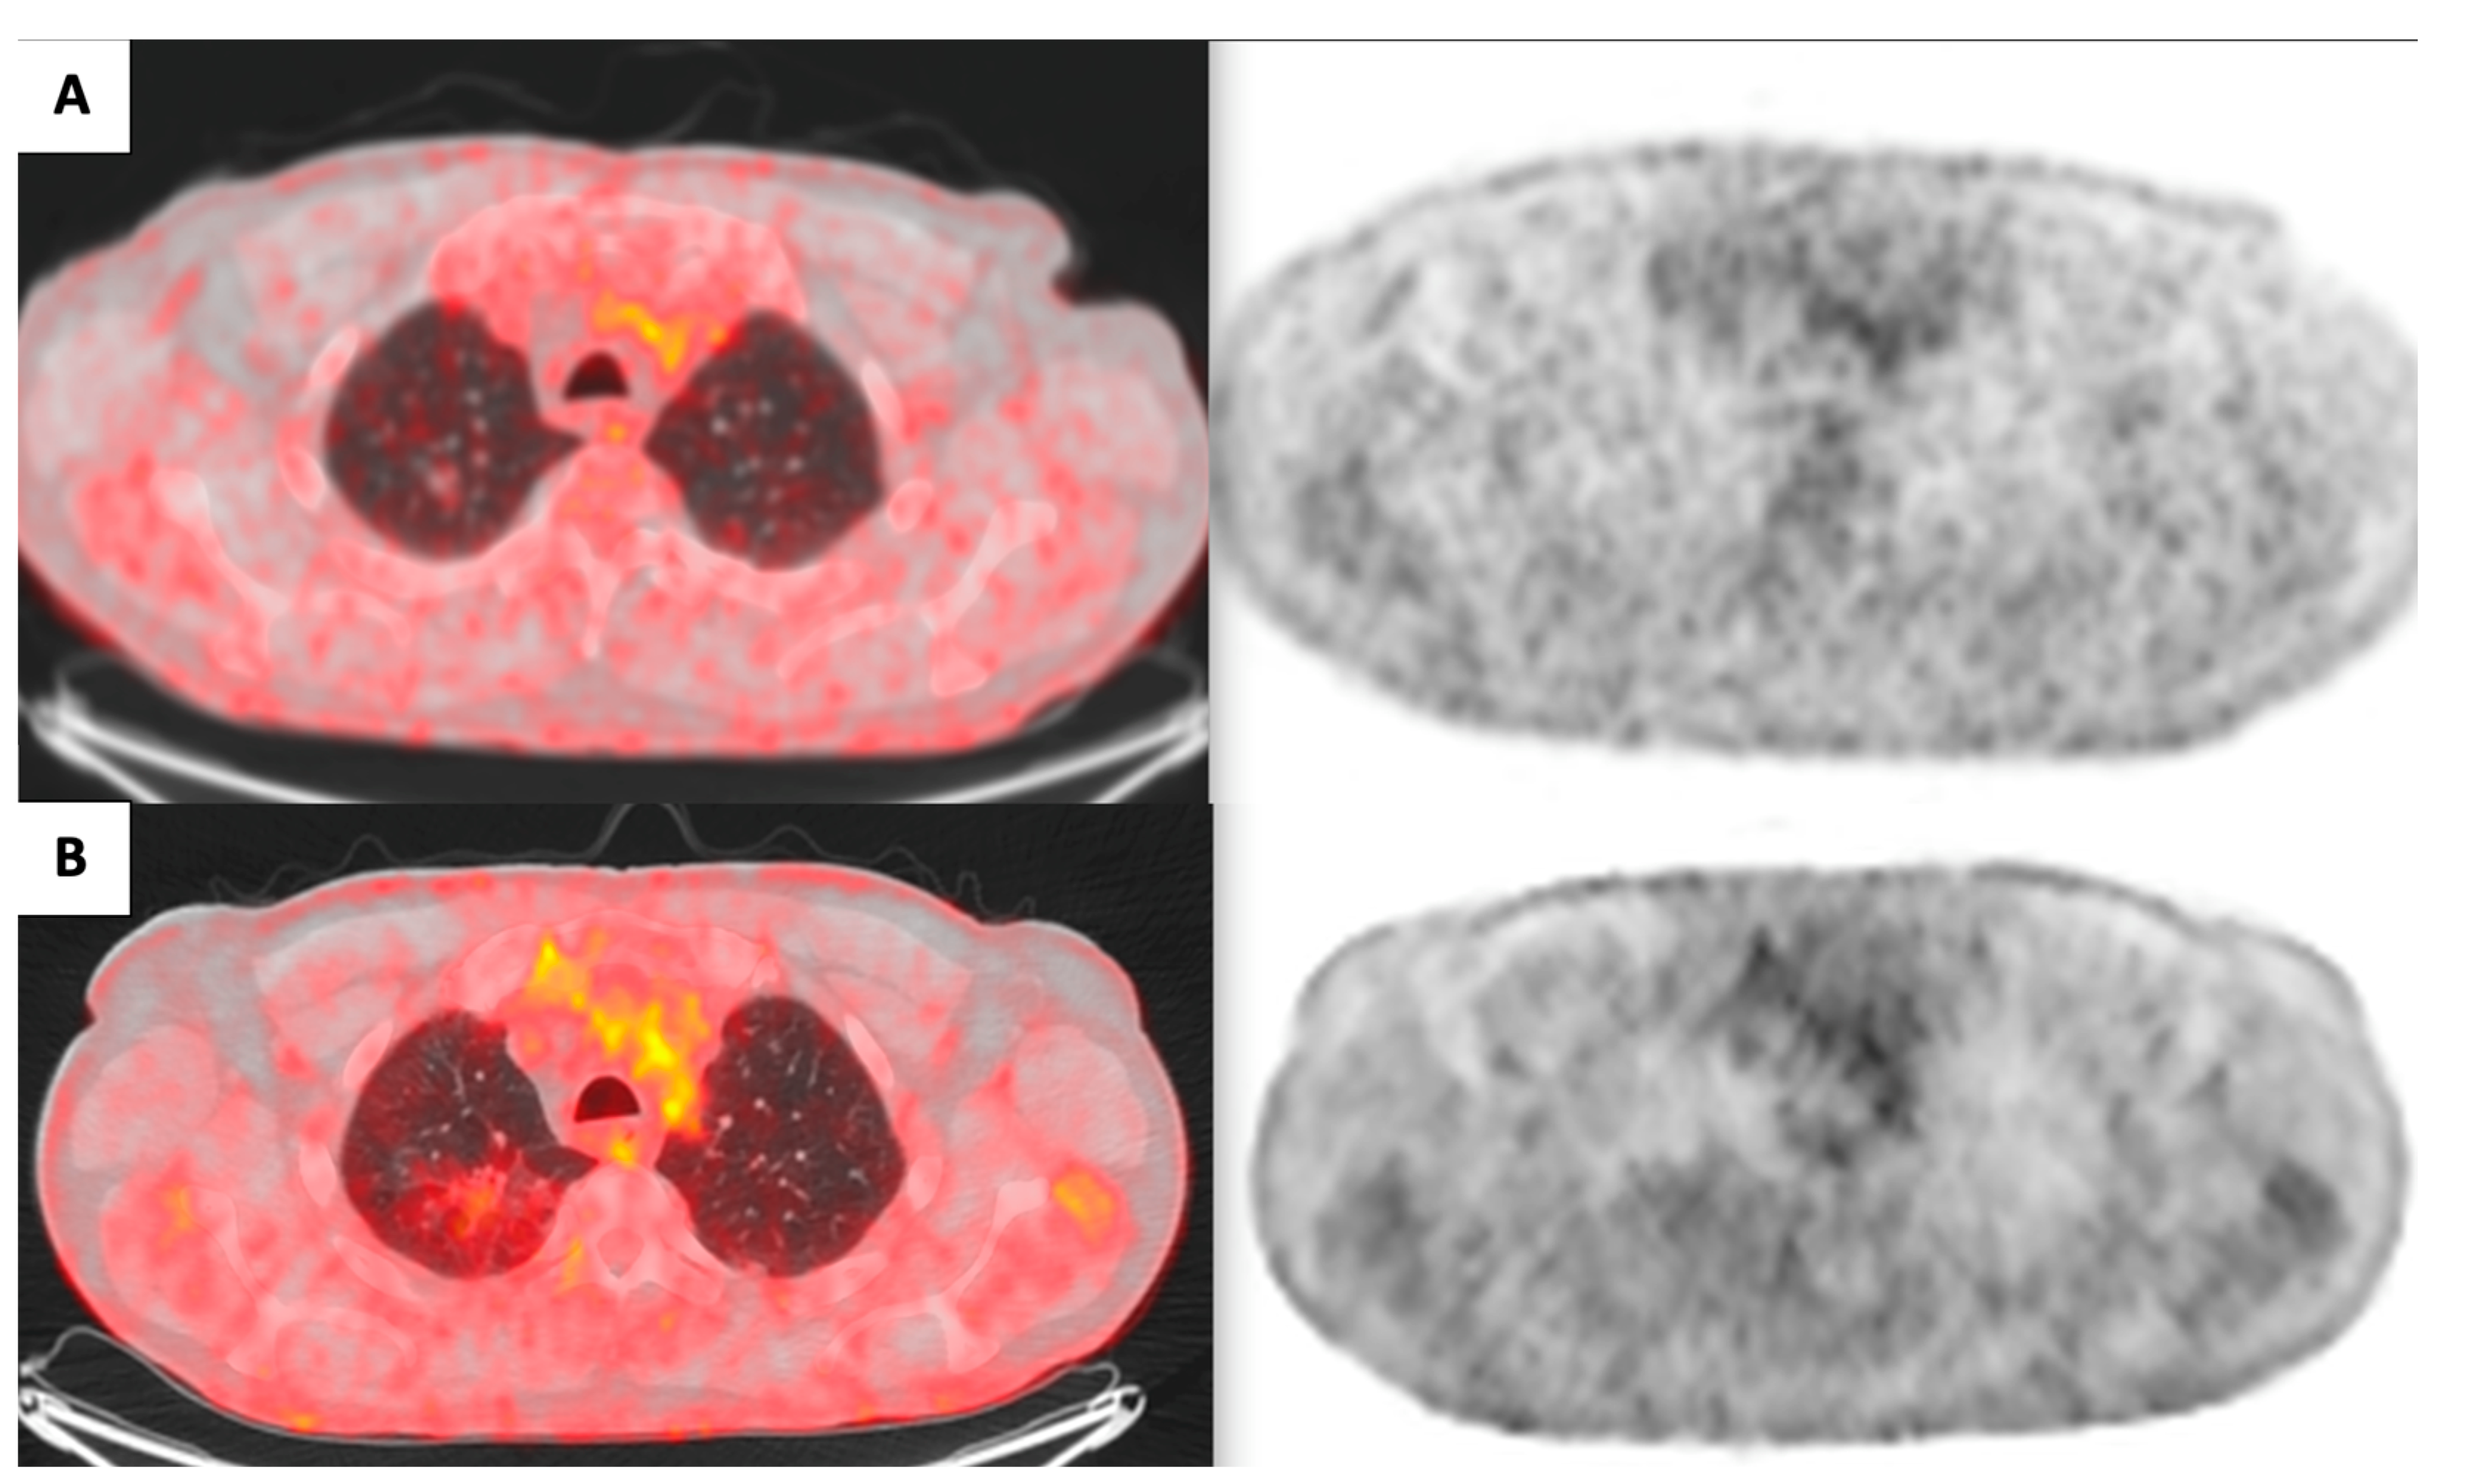

A 71-year-old male patient, a great former smoker without any noteworthy comorbidity, was enrolled in the BioMILD LCS program in 2015. The BioMILD was a prospective trial investigating the combination of LDCT and plasma microRNAs to enhance the effectiveness of LCS through tailored screening intervals and a personalized risk assessment [9]. At the baseline LDCT scan, less than 1 cm of pure GGO of the right upper lobe of the lung was noted. Previous CT scans of the patient have been retrieved and retrospectively reviewed, revealing the presence of the identified GGO in 2005, with minimal dimensional differences; therefore, the lesion was placed under surveillance. Over the years, the GGO was substantially stable, without significant dimensional or densitometric variations (Table 1). In 2020, the solid component seemed to increase, and an FDG-PET was performed, without pathologic tracer uptake. Therefore, surveillance was resumed. The next year, the result of the LDCT was astonishing: the known GGO developed into a 5 cm mixed GGO, with a consistent solid component (1 cm) and fissure shrinkage (Figure 1), presenting a volume doubling time (VDT) of 233 days. An FDG-PET was performed, showing an increased and diffuse tracer uptake within the pulmonary lesion (Figure 2). The patient was completely asymptomatic, without any sign of current or past infection, and was offered VATS surgical excision of the lesion, driven by the concern that the diagnosis might have been delayed too much. During the procedure, the GGO was not detectable; therefore, upfront right upper lobectomy and hylo-mediastinal lymphadenectomy were performed. The postoperative course was complicated by the occurrence of chylothorax on the first postoperative day (POD), which was conservatively managed through fasting, parenteral nutrition, and intravenous somatostatin, leading to progressive resolution. The chest drain was removed on the 15th POD, and the patient was discharged the next day in good clinical condition. The histologic examination revealed that the excised lesion consisted of a non-mucinous AIS of 1.2 cm, within a 4 cm area of fibrotic and congested lung parenchyma at stage pTis pN0 (0/25). Three years later, eighteen years after the first occurrence of the GGO, the patient is alive without evidence of disease.

Figure 1. Evolution of the right upper lobe lesion throughout the years ((A): 2005; (B): 2009; (C): 2011; (D): 2015; (E): 2016; (F): 2017; (G): 2018; (H): 2019; (I): 2020; (J): 2021).